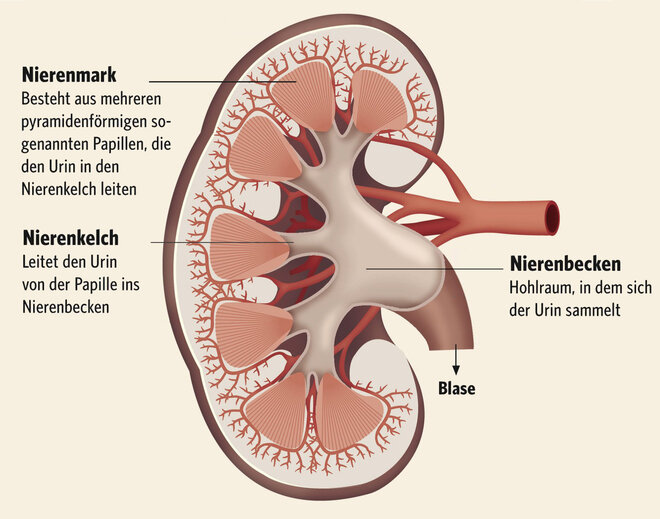

Bei der Glomerulonephritis handelt es sich um eine Entzündung der Nierenkörperchen (Glomeruli). Die Nierenkörperchen bestehen aus einer Art Gefäßknäuel in der Nierenrinde (siehe auch Hintergrundinformation weiter unten), in denen der sogenannte Primärharn gebildet wird. Unterteilt werden die Glomerulonephritiden in eine primäre oder sekundäre Glomerulonephritis. Handelt es sich um eine Entzündung der Nierenkörperchen, ohne weitere Systemerkrankung spricht man von einer primären Glomerulonephritis, ist die Entzündung dagegen Folge einer anderen Erkrankung außerhalb der Nieren, handelt es sich um eine sekundäre Glomerulonephritis.

Bei einer Nierenentzündung können aber auch die Harnkanälchen (Tubuli) und der sie umgebende Raum (Tubulointerstitium) entzündet sein, dann ist von einer tubulo-interstitiellen Nephritis die Rede. Als Folge davon treten Störungen in der Konzentrierung des Primärharnes auf.

Aufbau und Funktion der Niere